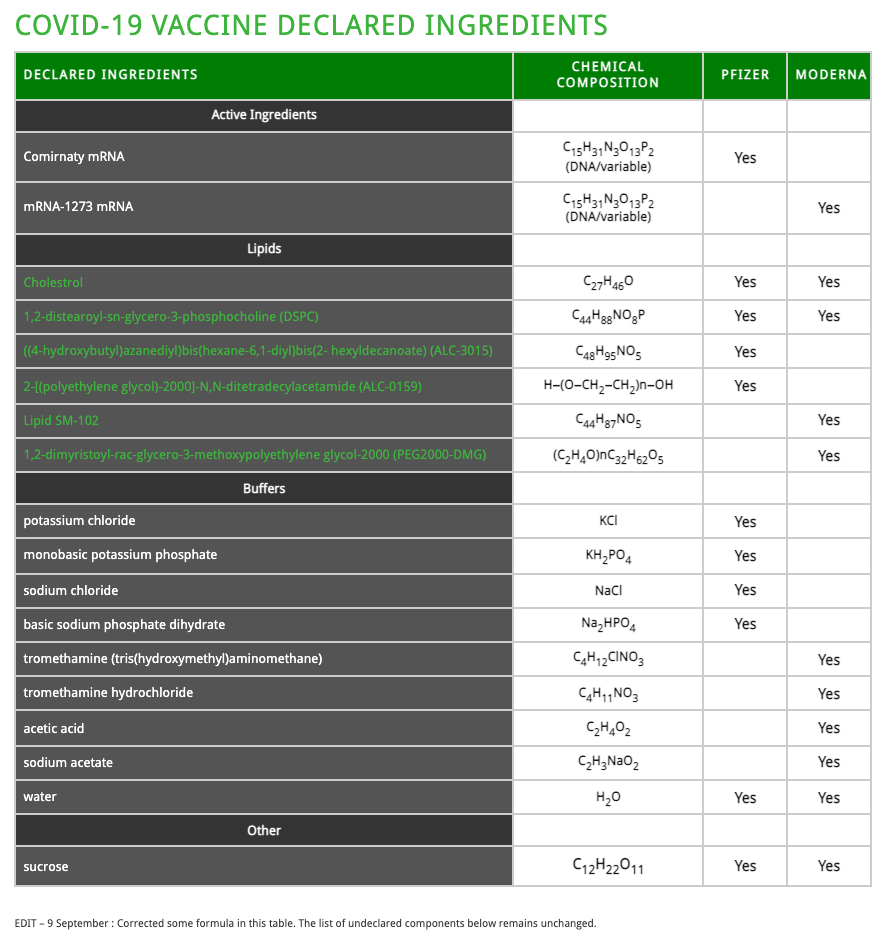

Abstract: Currently there are four major pharmaceutical companies who manufacture a SARS-CoV-2 now called SARS-CoV-19 vaccine. These manufactures and their vaccine are Pfizer–BioNTech mRNA Vaccine, the Moderna-Lonza mRNA-1273 Vaccine, the Serum Institute Oxford Astrazeneca Vaccine and the Janssen COVID -19 Vaccine, manufactured by Janssen Biotech Inc., a Janssen Pharmaceutical Company of Johnson & Johnson, a recombinant, replication-incompetent adenovirus type 26 expressing the SARS-CoV-2 spike protein.

The intended purpose of these vaccines are to provide immunity from the so-called infectious novel coronavirus or SARS-CoV – 2 virus now called the SARS-CoV – 19. These four pharmaceutical companies have not provided complete FDA disclosure on their vaccine box, insert fact sheet or label for many of the major and/or minor ingredients contained within these so-called vaccines. The purpose of this research article is to identify those specific major and minor ingredients contained in the Pfizer VaXXXine, the Moderna VaXXXine, the Astrazeneca VaXXXine and the Janssen VaXXXine using various scientific anatomical, physiological and functional testing for each SARS-COV-2-19 vaccine.